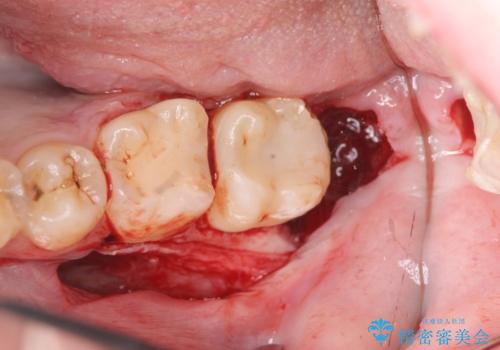

- 左下奥歯がしみるといらっしゃった方の症例です。

左下7の虫歯は深く、また歯冠高径も低かったため、歯冠長延長術を行いました。

術後歯肉の回復を待ち、左下6はセラミックインレー、左下7はオールセラミッククラウンにて補綴しました。